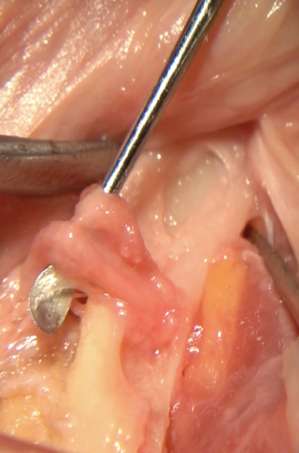

Dissezione e studio anatomico mandibolare.

Muscoli masticatori, nervi dentali, labbro inferiore, forame mentoniero e terminazioni del nervo mentoniero.

Studio del loop anteriore del nervo mentoniero in relazione al posizionamento implantare.

Esposizione del nervo alveolare inferiore e del nervo incisivo mediante osteotomia di accesso laterale eseguita con strumento piezoelettrico.